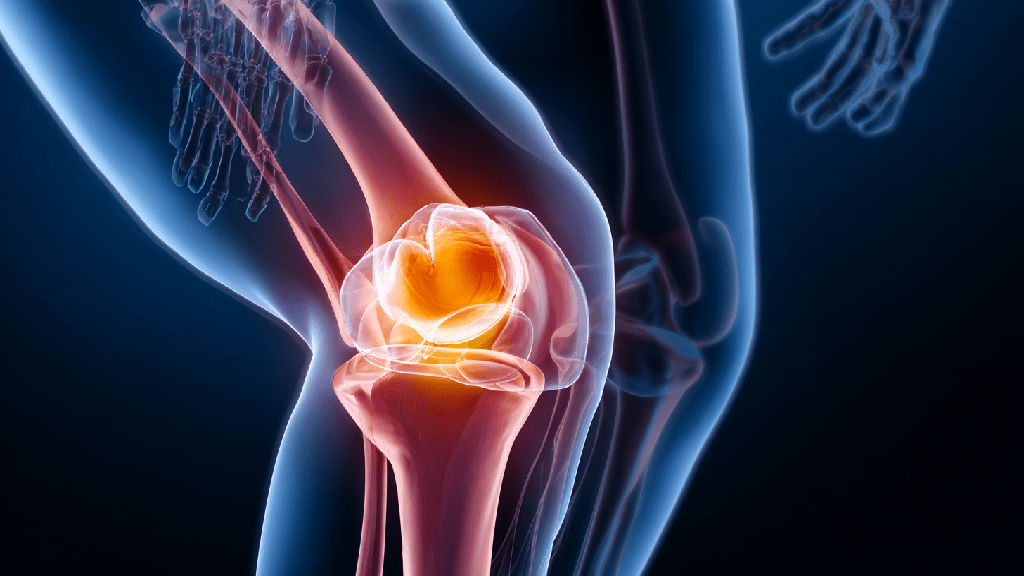

Представление об остеоартрозе как о простом «изнашивании» суставов с возрастом сегодня полностью устарело. Современная медицина рассматривает это заболевание как сложный, многофакторный процесс, в котором ключевую роль играет хроническое вялотекущее воспаление. Понимание этой природы открывает новые возможности для эффективного контроля над патологией. Ранняя диагностика и комплексный персонализированный подход позволяют не просто заглушить боль, а целенаправленно воздействовать на механизмы разрушения хряща, сохраняя активность и высокое качество жизни на долгие годы.

Остеоартроз (остеоартрит) — это хроническое прогрессирующее заболевание, при котором нарушается баланс между синтезом и деградацией тканей сустава. В основе лежит повреждение гиалинового хряща — гладкой, упругой структуры, обеспечивающей амортизацию и беспрепятственное скольжение костей. Постепенно в патологический цикл вовлекаются все элементы сочленения: субхондральная кость, синовиальная оболочка, связки, суставная капсула и окружающие мышцы.

В здоровом суставе процессы естественного обновления и разрушения хрящевой матрицы находятся в равновесии. При остеоартрозе это равновесие смещается в сторону катаболизма — преобладания разрушения. Хрящ теряет протеогликаны и воду, становится сухим, шероховатым, истончается. Его способность амортизировать нагрузку резко падает.

ВАЖНО: Ключевым звеном является синовит — воспаление синовиальной оболочки. Вырабатываемые при этом провоспалительные цитокины (интерлейкин-1, фактор некроза опухоли-альфа) стимулируют выработку ферментов, разрушающих коллаген и протеогликаны хряща. Таким образом, формируется порочный круг: повреждение → воспаление → дальнейшее разрушение.

В ответ на хроническую перегрузку и воспаление активируются костеобразующие клетки. По краям суставных поверхностей формируются костные шипы — остеофиты, которые изначально являются попыткой организма стабилизировать сочленение, но в итоге ограничивают движение и травмируют окружающие ткани.

Деформирующий остеоартроз

Деформирующий остеоартроз представляет собой форму заболевания с преобладанием анатомических изменений. В процессе прогрессирования нарушается ось конечности, изменяется форма контактных поверхностей, формируются массивные остеофиты. Чаще поражаются коленные и тазобедренные сегменты, что напрямую отражается на походке и способности к передвижению.

Развитие деформирующего остеоартроза связано с длительной перегрузкой, ожирением, перенесёнными травмами и системным воспалением. Клинически состояние проявляется стойкой болью, выраженным ограничением движений и значительным снижением качества жизни.